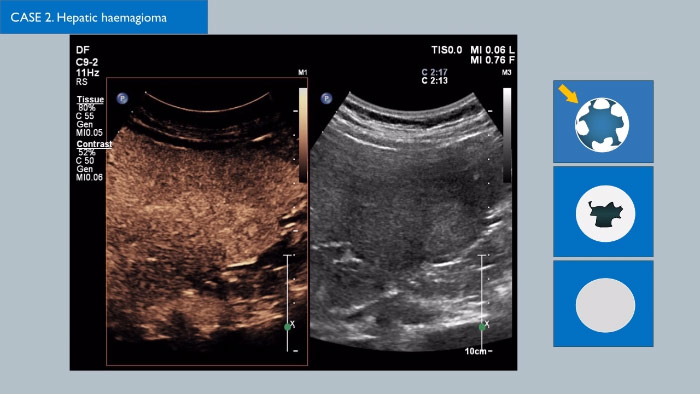

Los agentes de contraste para ultrasonidos pueden transformar el papel que desempeñan los ultrasonidos, pues permiten que los profesionales sanitarios estudien los patrones de mejora de las lesiones hepáticas en tiempo real, lo que ofrece la posibilidad de realizar diagnósticos más definitivos y rápidos.

Con los ultrasonidos de Philips, los ultrasonidos con contraste se integran a la perfección en el flujo de trabajo normal y proporcionan un nivel de detalle excepcional en exploraciones de la fase arterial, portal y tardía. Además, gracias a tecnologías avanzadas como MaxVue, el transductor PureWave C9-2, las imágenes de fusión, la cuantificación integrada mediante las Q-App de Philips y la solución hepática definitiva, ya es posible sentir una seguridad total incluso en las exploraciones más complicadas. Soluciones innovadoras como la tecnología xMATRIX 3D/4D también pueden dar un giro a la evaluación de las lesiones hepáticas, pues proporcionan un método rápido y eficaz de visualizar los vasos nutricios y la respuesta al tratamiento. Existen multitud de avances fascinantes en el campo de los CEUS; haga clic en el enlace para ponerse en contacto con su representante local de Philips.